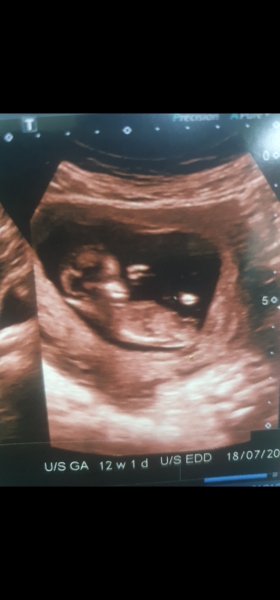

Can anyone tell with my one taken at 12.3 yesterday? X

Hi can anyone please tell me , it's boy or girl ? 12 week 1